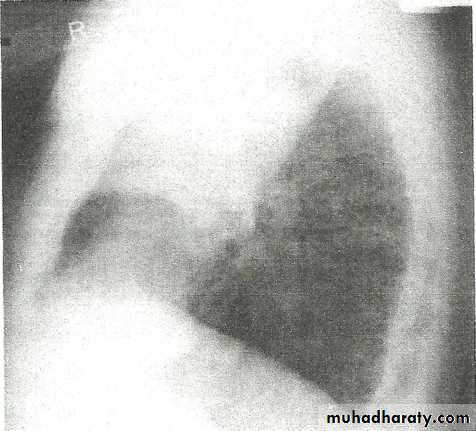

• Right lower lobe consolidation - Lat.

• The density lies posterior to fthe oblique issure- the position of the lower lobe.